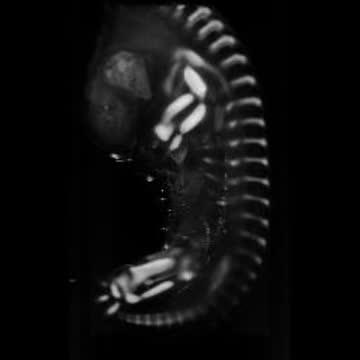

3-D Imaging Developing Cartilage

video: Gene expression and 3-D imaging helps to visualize the developing cartilage.avi. view more

Credit: Professor Paula Murphy, Trinity College Dublin.